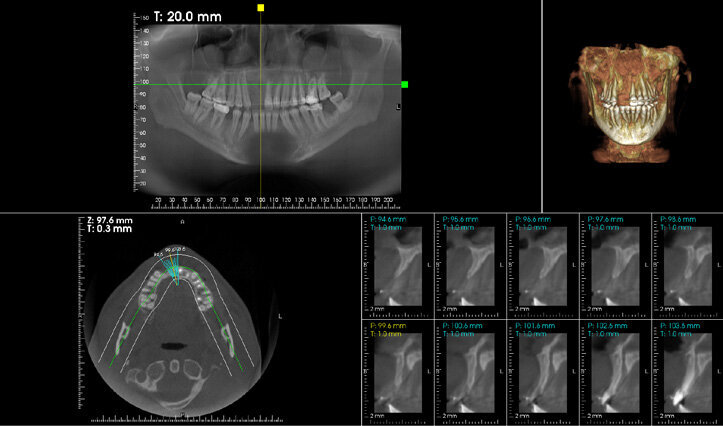

Figure 11: CBCT cross-sectional view of sites no 7 and 8 revealed inadequate ridge width to support implant with restoration.

Figure 12: Preoperative view showing the amount of horizontal bone deficiency in the area.

A 33 years-old male patient was visiting our clinic to replace missing teeth no 7 and 8. He was medically fit and mentioned that his teeth were lost due to car accident few years back. Intraoral examination shows absence of space for implant placement and restoration, orthodontic treatment was conducted for 18 sessions followed by surgical implant placement after stabilization of the occlusion. Following the restoration of the space, the amount of horizontal bone loss was evident both clinically and on CAT examinations (Fig.10, 11). A linear incision with mucoperiosteal flap elevation were conducted, the amount of horizontal bone loss was advanced (Fig. 12), which was an indication for autologous bone graft, patient refused to undergo an invasive surgery so PRF associated bovine bone was planned in the area. Blood withdrawal and centrifugation were done with preparation of both L-PRF membranes and sticky bone (bovine bone associated PRF) (Fig.13, 14,15). The combination was placed on the host bone deficiency and covered by a first layer of L-PRF membranes in order to stabilize the graft and insure hemostasis, the second layer of L-PRF membranes covered the cross linked collagen membrane placed in the same area and covering the first entity (Fig.16).